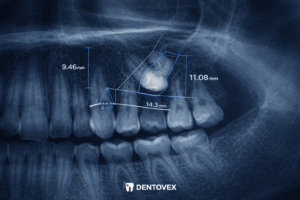

- Panoramic X-rays: This 2D view provides a broad overview of all teeth, showing their position relative to the jawbone.

- CBCT (3D Imaging): This is the “gold standard” for impacted teeth. A 3D scan allows the orthodontist to see the exact depth and angle of the tooth—whether it’s on the “palatal” side (roof of the mouth) or the “labial” side (near the lips). This precision is vital for the surgeon to know exactly where to make the incision.